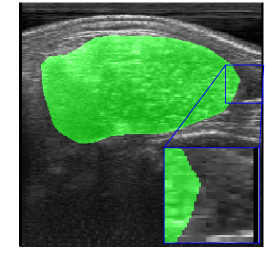

Figs. 2 and 3 present examples that illustrate the challenges of semantic segmentation methods. The trees in Fig. 2 show that in most images the foreground covers fewer pixels than the background (class imbalance). Besides, trees have edges that are difficult to label, and some pixels may be incorrectly labeled. Fig. 3 also illustrates the labeling challenge, in which some parts of the object are not visible in the image due to noise when capturing images.

Rib Eye Area (REA). This image dataset consists of ultrasound images of the Longissimus dorsi muscle between the 11th and 13th ribs of cattle. The goal is to automatically calculate the rib eye area (REA), an important region for decision making during cattle breeding. The main challenge is the uncertainty in the REA annotation, since the image is noisy and even experts have difficulty in delimiting the borders of this region. Fig. 3 presents examples of images and the annotation made by a specialist. We can observe that some borders are absent and depend on the subjectivity and knowledge of the annotator. To evaluate the segmentation methods, 76 images with resolution were obtained and labeled by an expert. Due to the number of images, the division of the images in training and testing followed 5-fold cross-validation.

REA dataset. This image dataset has high uncertainty during labeling due to noise from the ultrasound image. In some cases, the border of REA is not completely visible and must be estimated by the specialist. Therefore, the proposed approach becomes essential to obtain accurate segmentation at the edges. The segmentation examples in Fig. 6 show that the baseline was not able to define the REA correctly due to the uncertainty of the labeling. On the other hand, the proposed approach presents results close to the specialist in regions that the border needs to be estimated.